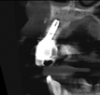

In this case, a dental implant that had been placed 10 years prior was functional, stable, and esthetically acceptable to the patient. However, a significant fistula was present on the facial-apical aspect of the ridge in the maxillary lateral incisor area. This area was painfully sensitive to touch and demonstrated purulence when squeezed. To evaluate the lesion, first, a conventional digital radiograph was acquired, which revealed an apical radiolucency at the apex of the implant (Figure 1). Further analysis using cone-beam computed tomography (CBCT) demonstrated a fistula from that site to the oral environment (Figure 2). Treatment options were discussed, including removal of the implant, followed by grafting, a healing period, and replacement of the implant and implant-retained crown. If this option was selected, a transitional appliance would need to be created. Another option was to attempt to salvage the implant and implant crown by treating the infection and grafting the site to create a new boney wall and eliminate the fistula. Ultimately, the patient accepted this option to attempt to salvage the fixture and crown.

(1.) Preoperative radiographic evaluation demonstrating a large radiolucency at the apical third of the body of an implant fixture replacing the patient’s maxillary left lateral incisor. The implant was stable, and the prosthesis was deemed esthetically acceptable by the patient.

Figure 1